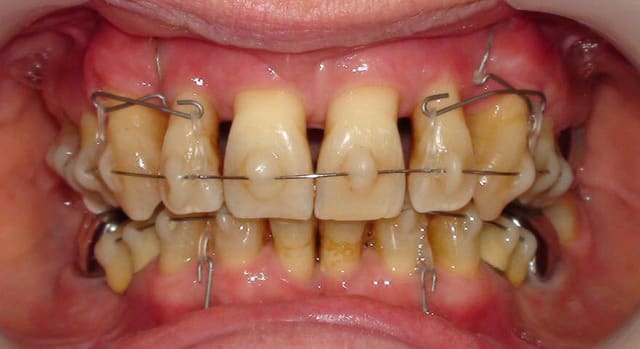

Voici une images plus explicite. Je crois que les libellules ne sont pas décrites dans l'article que tu cites mais elles le sont d’une manière succincte dans celui que j'ai publié en septembre dernier dans "L'Orthodontie Française". Donne-moi en MP tes coordonnées et je t‘enverrai par mail une planche explicative de leur fabrication, celle qu’on donne quand on fait des TP.

merci daniel, c'est tres clair. je voyais la libélule comme un ressort TMA d'ingression, alors que c'est plus un support pour les chainettes, qui sont donc la force intrusive.

Pas tout à fait..

À l’arcade supérieure, la force d’ingression était donnée uniquement par le ressort TMA en forme de libellule, les chaînettes servant uniquement de liaison. Celles-ci ont été utilisées par facilité, nous aurions tout autant pu employer des ligatures métalliques que nous aurions changées ou raccourcies au fur et à mesure de l’ingression. Le ressort lui-même n’a pas eu besoin d’être réactivé.

À l’arcade inférieure, ce sont les chaînettes elles-mêmes qui ont fourni les forces d’ingression.